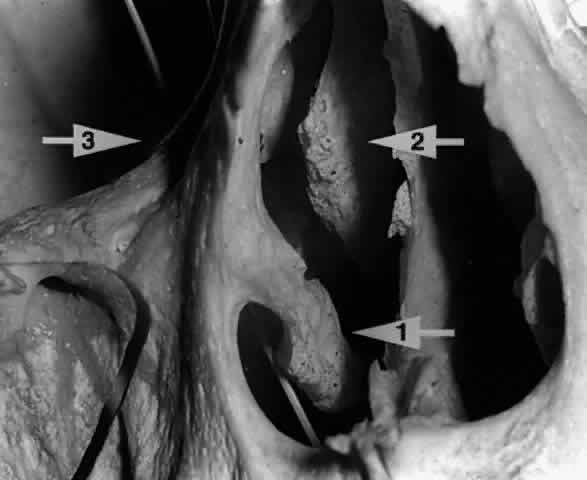

In some cases, the nasolacrimal duct may empty directly into the roof of the inferior meatus, but in the majority, the opening is on the side wall of the inferior meatus (Fig. 22), 30 mm behind the lateral margin of the anterior nares. In children and infants, the opening is found 20 mm behind the lateral margin of the anterior nares. In a small number of cases, the nasolacrimal duct is found to course beneath the mucosa of the lateral nasal wall without opening into the nose.24,25

Fig. 22. A twig placed in the right nasolacrimal fossa of this skull is seen exiting below the inferior turbinate (arrow 1). The middle turbinate (arrow 2) is seen lying medial to the nasolacrimal fossa (arrow 3).

The middle turbinate is an outcropping of the ethmoid bone and may project anteriorly into the nasal cavity to lie medial to the lacrimal fossa19,28 (see Fig. 22). Clinically, on occasion, the anterior portion of the middle turbinate must be excised during dacryocystorhinostomy to establish an unobstructed osteotomy.